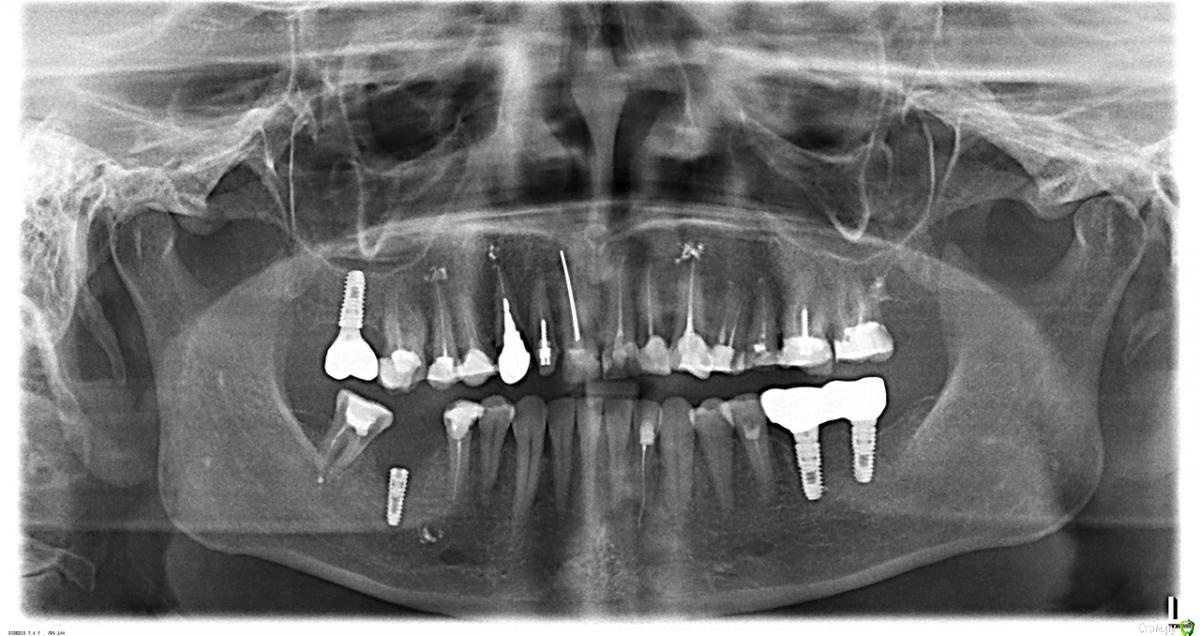

Наталия1966 Опубликовано 1 ноября, 2019 Автор Поделиться Опубликовано 1 ноября, 2019 Покажите хотя бы фото этого имплантатаНу, вот они все. Вчерашний снимок остался в клинике. Ссылка на комментарий

Наталия1966 Опубликовано 1 ноября, 2019 Автор Поделиться Опубликовано 1 ноября, 2019 Это когда специалисты, у которых Вы просите совета, пишут ВамА Вы на это отвечаетеЯ не стоматолог и пишу просто по ощущениям во рту. Я сама себе, как вы говорите, "удалить имплант" не смогу, ну, никак. Я просто спросила, что там может быть и какова судьба. Вчера мне поставили формирователь десны и предупредили, то спереди имплант обнажен до половины, но он интегрирован ниже этой половины, то есть, не дал проворота, когда его машинкой пытались провернуть. И врач новенький, тот уехал, дал шанс, что, в принципе, если гноя после формика пройдет, то... с ним можно как то жить. Предыдущий набедокурил-то, а этому расхлебывать. Спереди не хватает кости и это НЕ СКОЛ. То есть, так изначально установлен! Хотя я спрашивала. Какой то бабуле в очереди дистрактором переднюю стенку подымали в другом городе - "Такой винт, его крутить надо было каждый день". И подняли! И три импланта стоят у нее лет пять или десять. Ссылка на комментарий

Наталия1966 Опубликовано 12 ноября, 2019 Автор Поделиться Опубликовано 12 ноября, 2019 у Вас есть телефон с камерой и зеркало Нету у меня ничего. Поставили формик, промучилась сколько то пришла еле еле на конс и чистку к новому доктору, хотела уходить уже в другую клинику. Думала аферисты и все такое, но нет. Молодой доктор сообщил, что повреждение незначительное семерки было до имплантации, что просто поправить стенку и все, что зуба не лишусь. Что выждать время, если через месяц снимем формик и десневой край не сформируется, то тогда будем решать, что делать, чтобы я не истерила раньше времени. Что наличие гнойного отделяемого серьезный момент, но он может быть устранен заживлением при установленном формирователе. Если не сформируется край, то необходимо поднимать спереди кость на частичном обнажении и не факт, что прирастет блок или титановая сетка поможет, неизвестно с чего идет гной. Даже при обнажении гноя не должно быть. Вообщем до 24 числа меня отпустили. Ниче не болит жую формиком молочу. Пока так. 1 Ссылка на комментарий